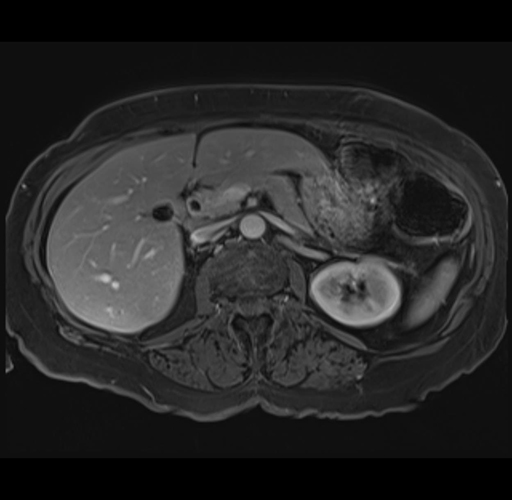

MRI T1